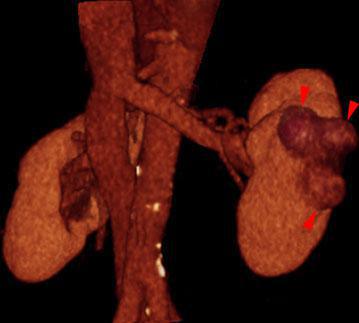

Hipernefroma 2